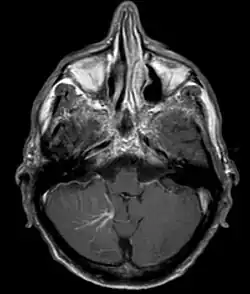

Developmental venous anomaly in the cerebellum seen on axial contrast-enhanced T1 weighted MRI

A developmental venous anomaly (DVA, formerly known as venous angioma) is a congenital variant of the cerebral venous drainage. On imaging it is seen as a number of small deep parenchymal veins converging toward a larger collecting vein.

DVA can be characterized by the caput medusae sign of veins, which drains into a larger vein. The drains will either drain into a dural venous sinus or into a deep ependymal vein. It appears to look like a palm tree.[1]